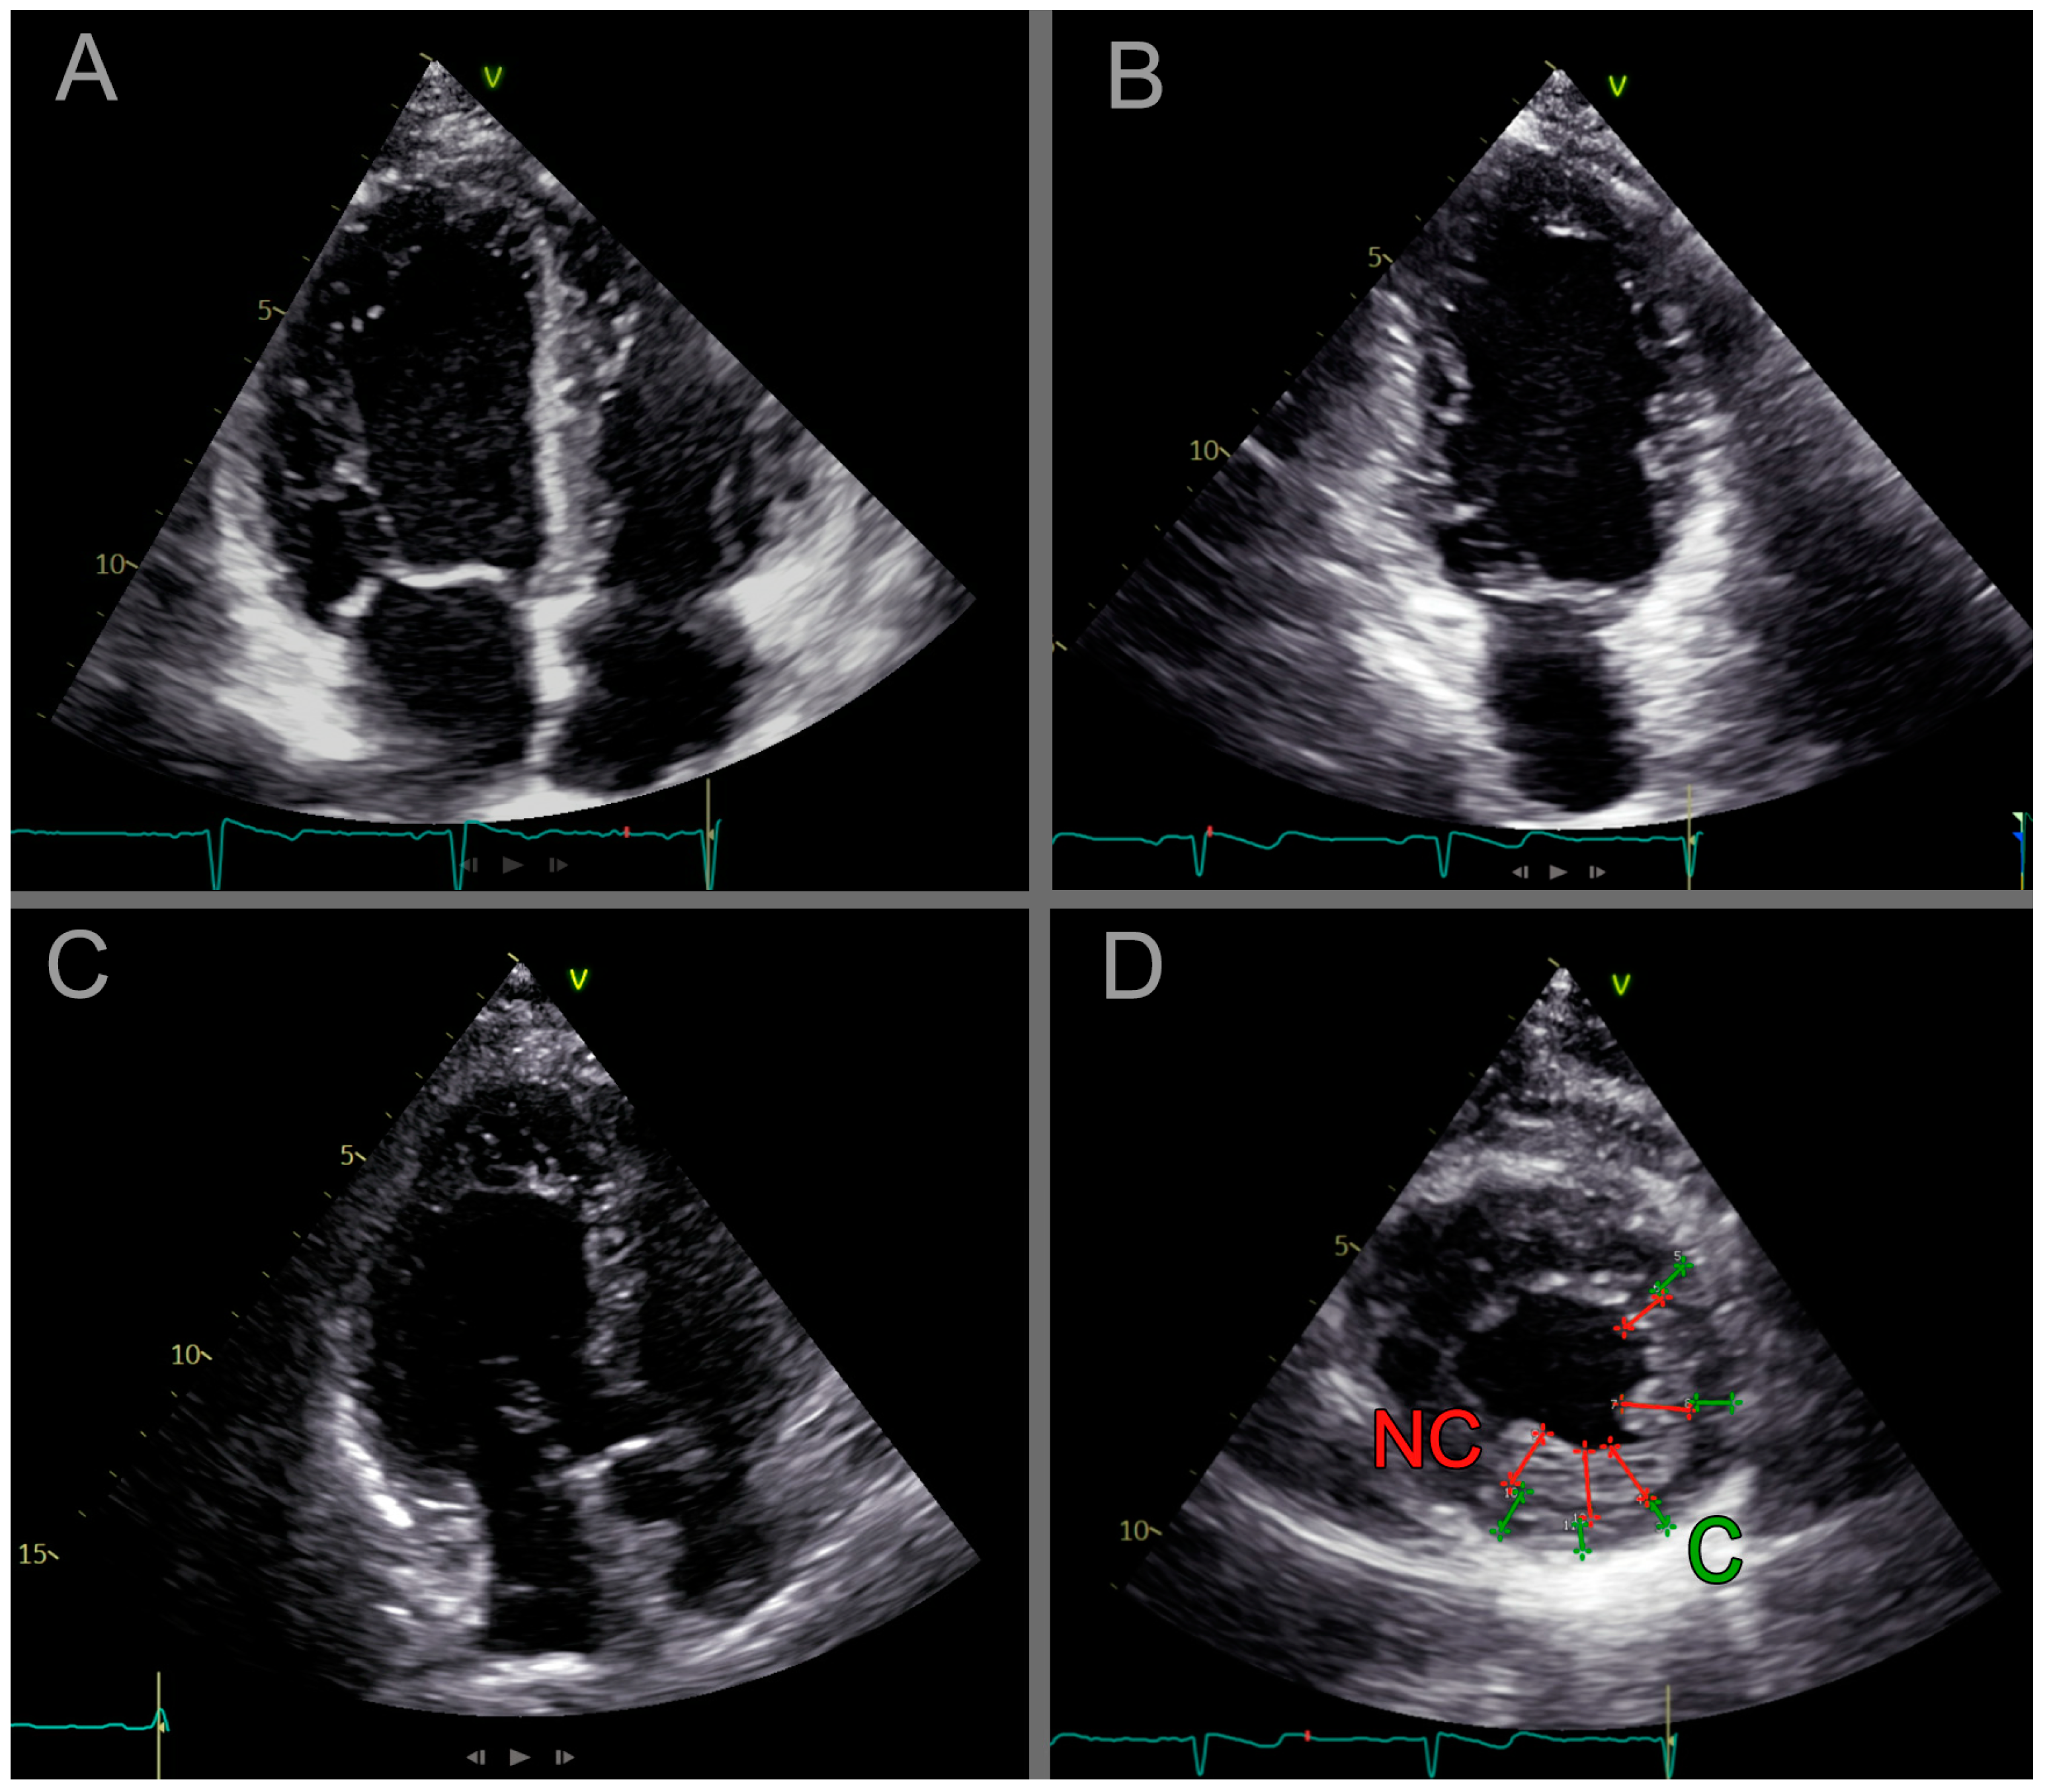

2.2.3. Cardiac Ultrasound

| JENNI-pos | Blood relatives, who fulfilled the LVET ultrasound criteria according to Jenni |

| JENNI-neg | Blood relatives, who did not meet the LVET ultrasound criteria according to Jenni |

- Jenni, R.; Oechslin, E.; Schneider, J.; Attenhofer Jost, C.; Kaufmann, P.A. Echocardiographic and pathoanatomical characteristics of isolated left ventricular non-compaction: A step towards classification as a distinct cardiomyopathy. Heart 2001, 86, 666–671. [Google Scholar] [CrossRef] [PubMed]